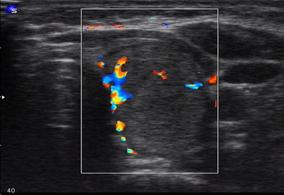

. “Большими” диагностическими

признаками, сочетание которых позволяет установить диагноз АИТ, являются:

первичный гипотиреоз (манифестный

или стойкий субклинический);

наличие антител к ткани щитовидной

железы и ультразвуковые признаки аутоиммунной патологии (Рис 2).

Рисунок 2. УЗ-картина аутоиммунного тиреоидита